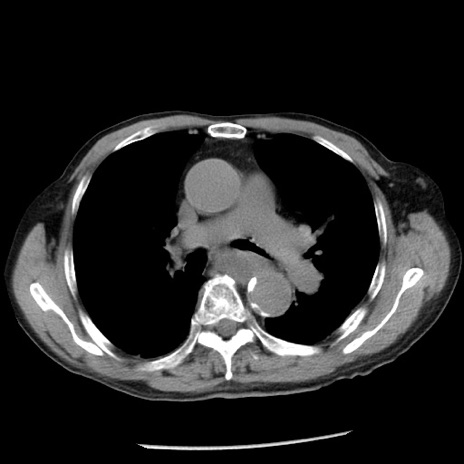

症例26(横断像)

【症例】80歳代男性

【主訴】嘔吐

【現病歴】昨晩2回嘔吐あり、今朝になっても嘔吐あり。来院。

【既往歴】胃潰瘍

【身体所見】意識清明、BT 37.6℃、BP 166/95mmHg、HR 100bpm、SpO2 97%、腹部:平坦・軟、腸蠕動音聴取良好、圧痛なし。

【データ】WBC 21900、CRP 1.46